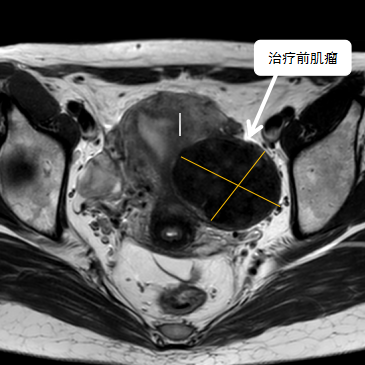

術前影像資料

經過兩個月的藥物預處理,完善術前準備,治療當天陳主任帶領團隊在3.0T磁共振清晰圖像引導下對子宮肌瘤進行精準消融,患者全程清醒,沒有明顯疼痛,經過1個多小時的精細操作,手術非常成功,消融率接近90%,內膜未見損傷!觀察一個小時后患者即自行回家。

術后即刻行增強磁共振檢查,顯示病變被消融近90%,內膜未見損傷